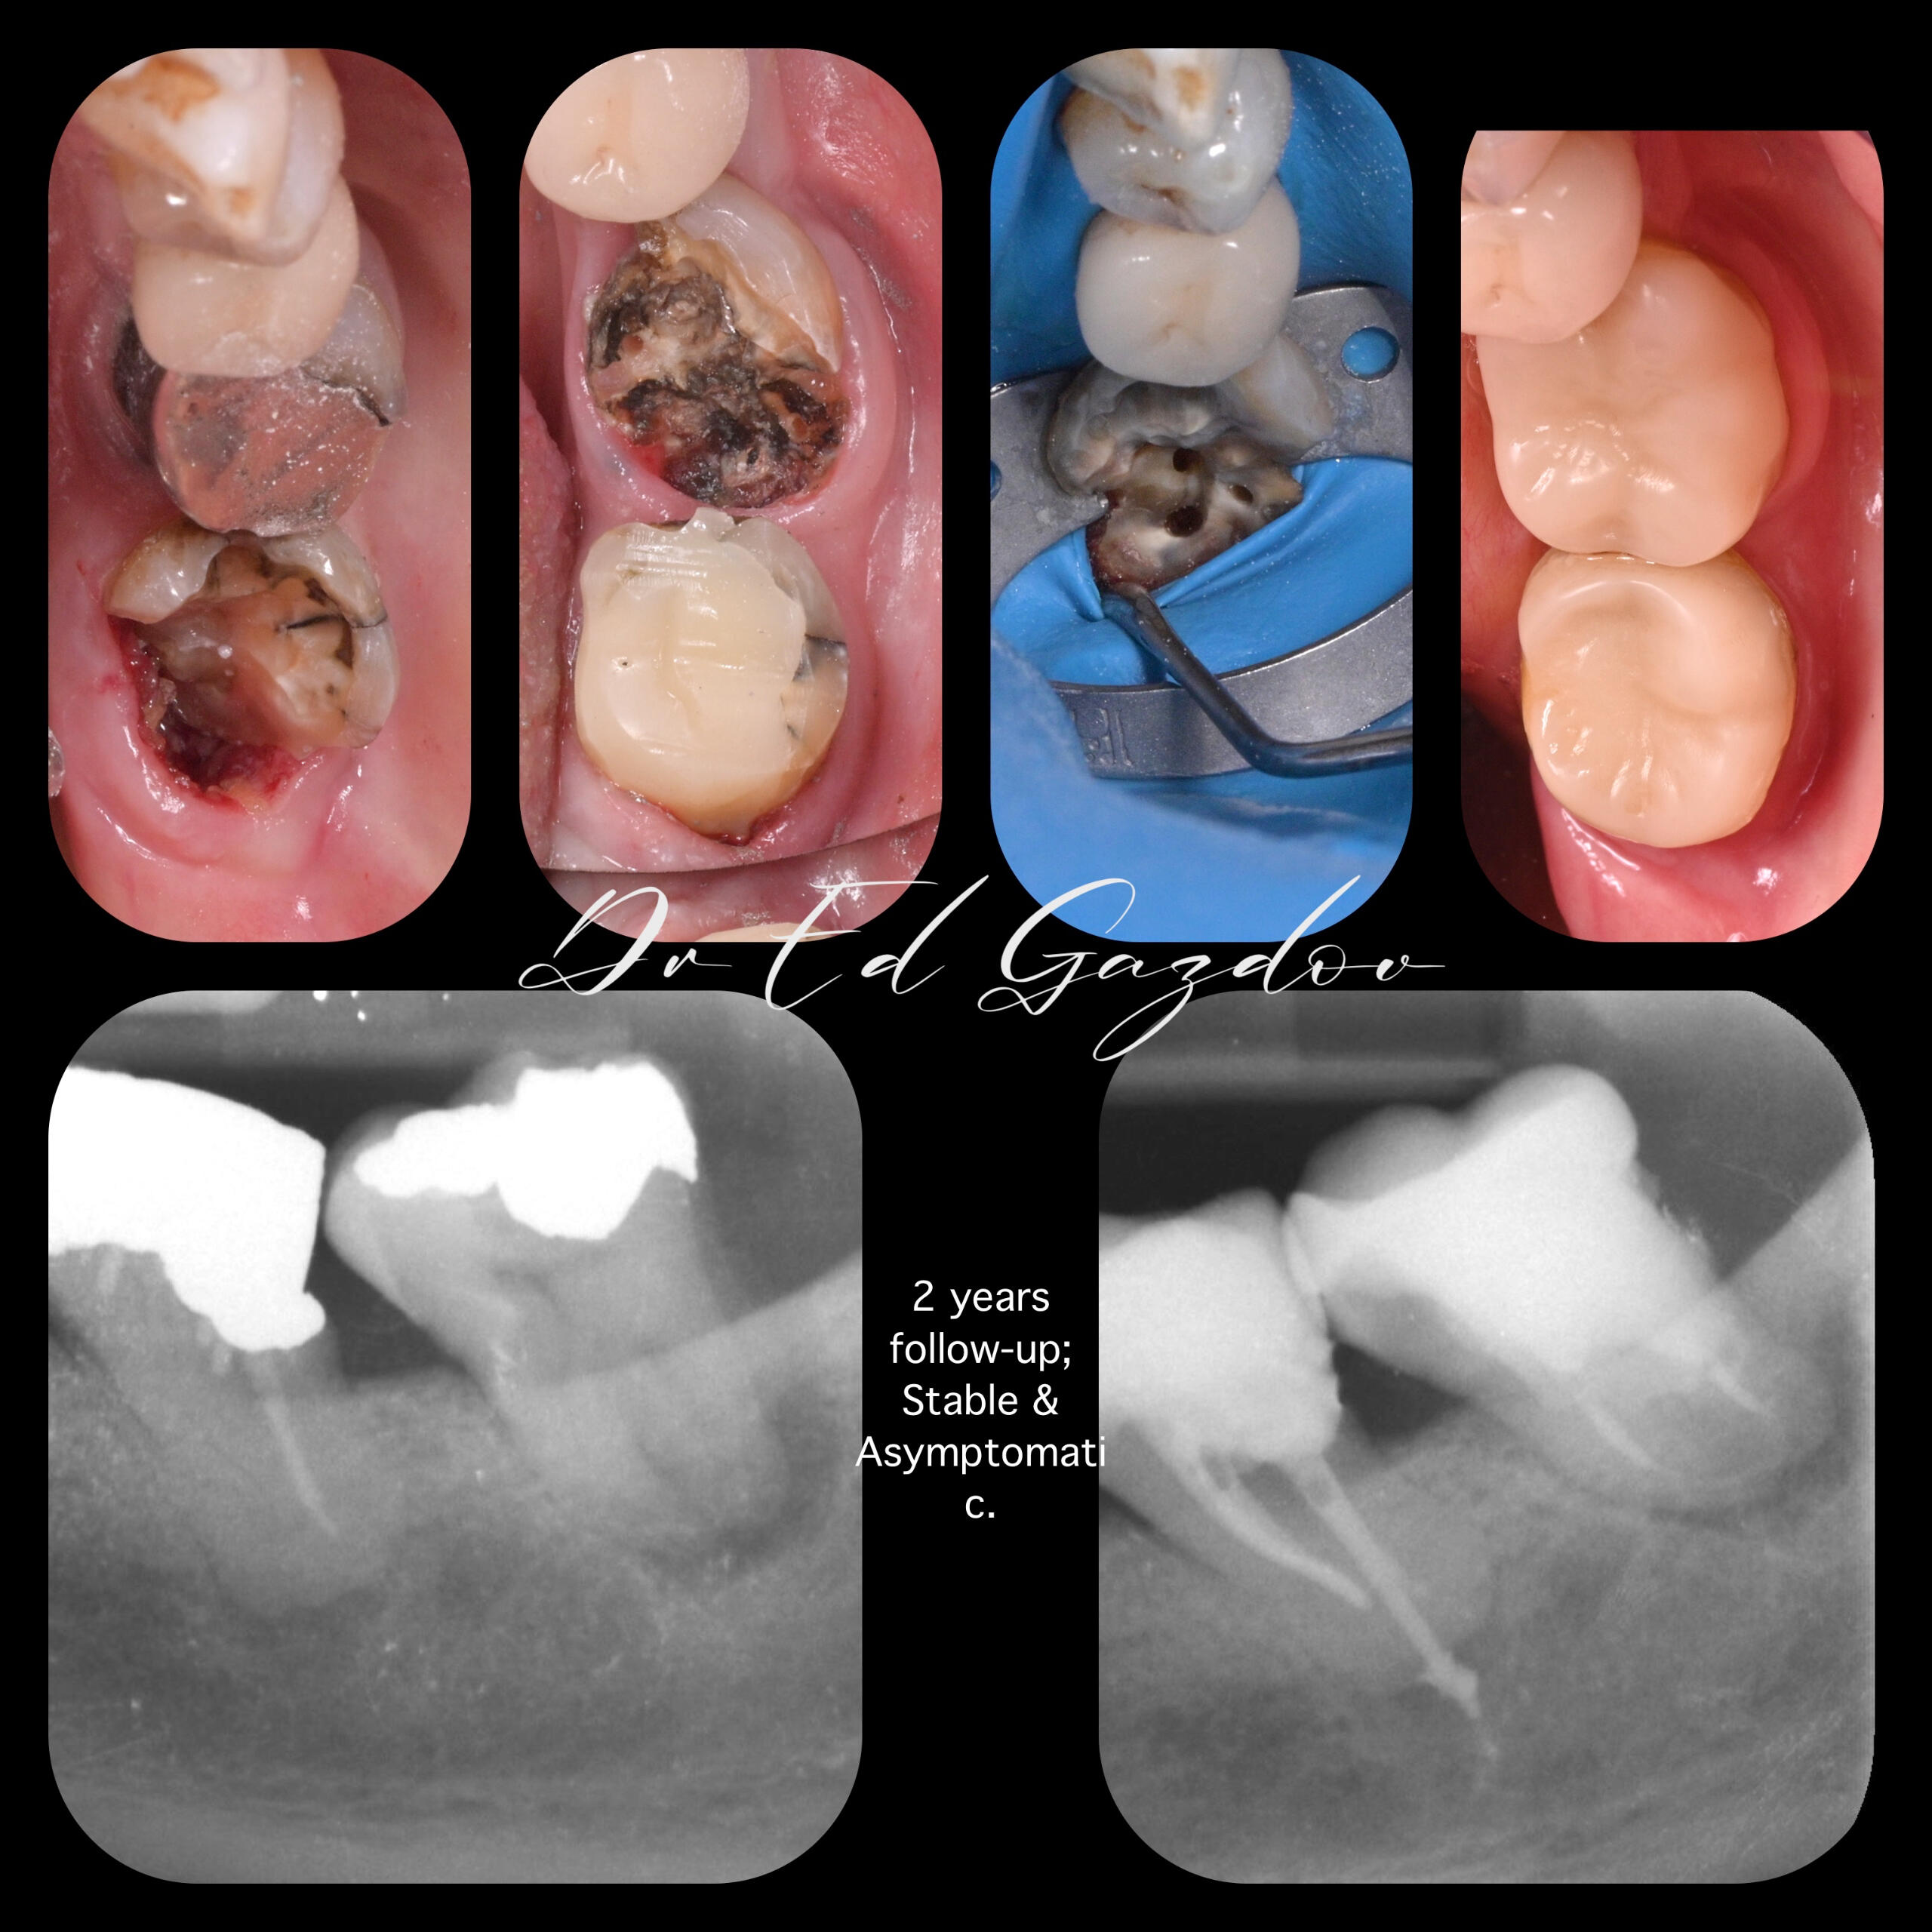

ПРЕДИ И СЛЕД

🦷 Истински резултати. Истински хора.Всяка усмивка, която виждате тук, е реален случай, лекуван лично от Д-р Едуард Газдов – от първия преглед до последната фина настройка.Работим с внимание към детайла, с модерни и щадящи методи, и с лично отношение към всеки пациент. Независимо дали става дума за пълна трансформация, единичен зъб или сложно релечение – подходът ни е прецизен, внимателен и изцяло съобразен с нуждите Ви.⸻🛠️ Какво предлагаме:

• Лечение на сложни коренови канали

• Зъби в същия ден – кореново лечение, изграждане, дигитален дизайн и поставяне на корона в едно посещение